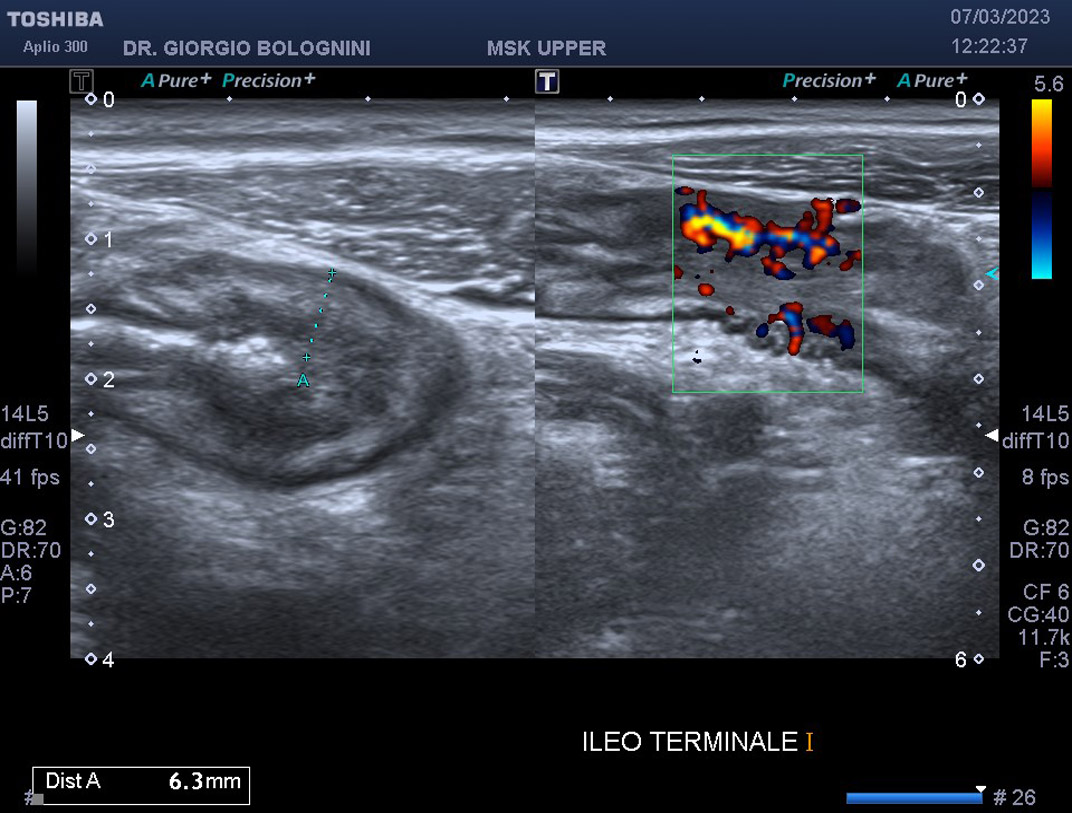

CASO 17 - MORBO DI CROHN

malattia infiammatoria dell'intestino